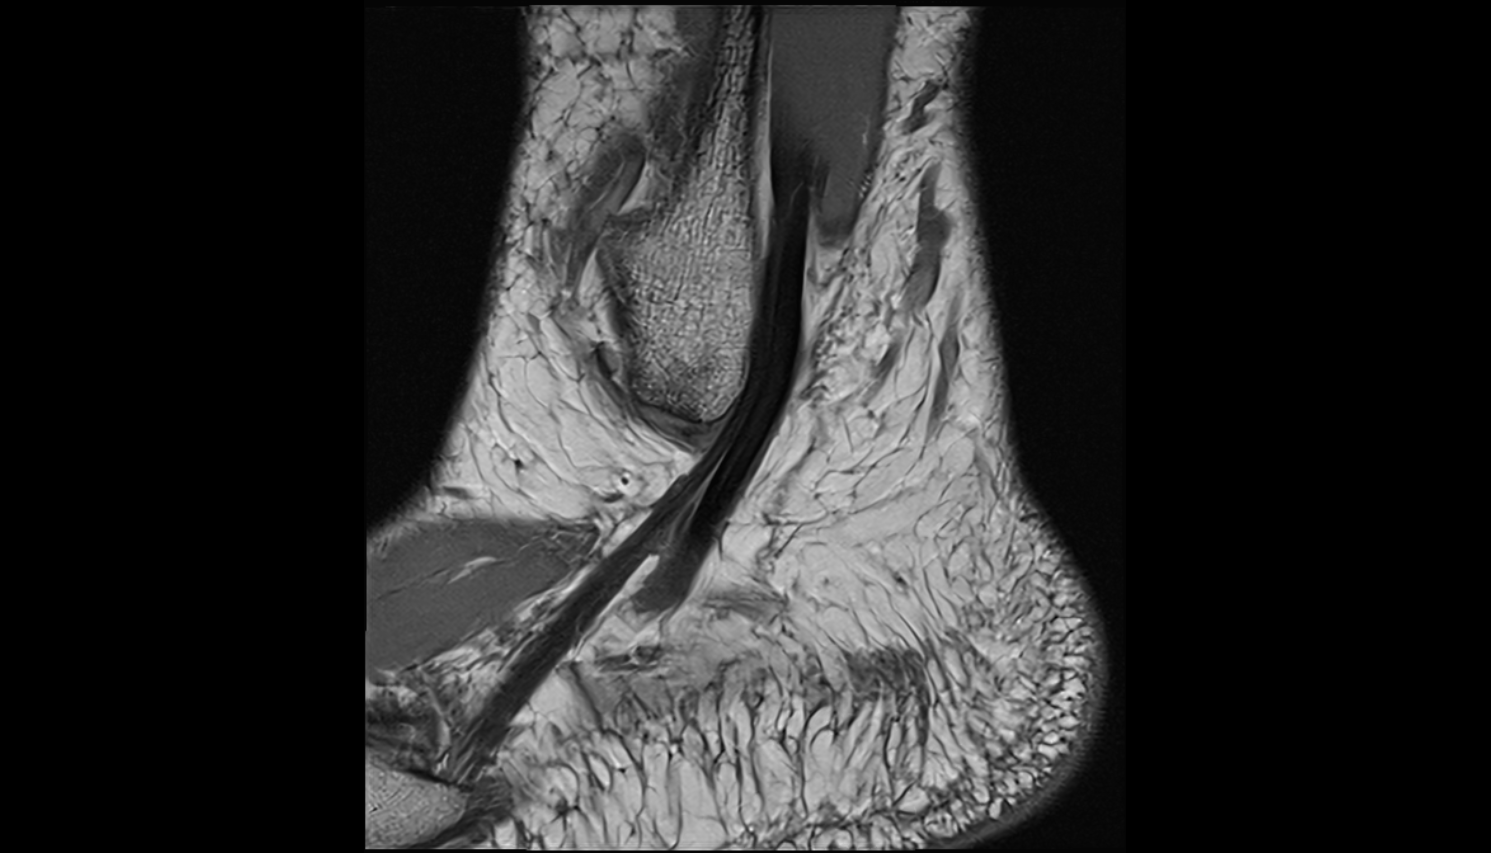

- Achilles tendon

- Calcaneus

- Talus

- Ankle joint